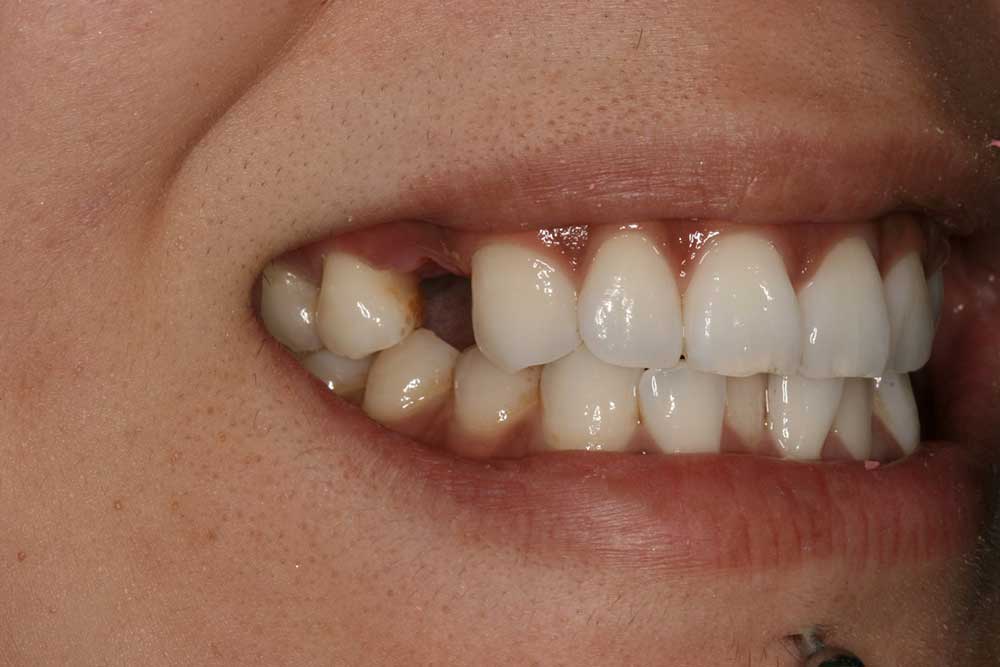

Anthony A.

This patient had only a few remaining infected teeth, but didn’t want to settle for just a denture.  Placed multiple implants and provided a secure fixed option which allowed him to not only chew better but to smile again.